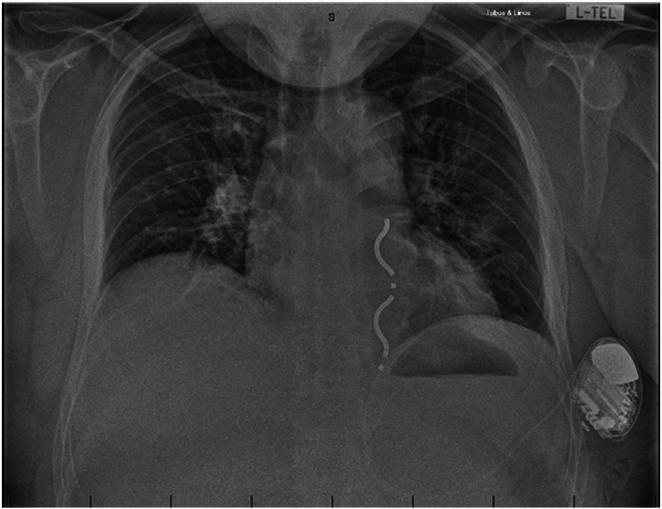

Extravascular defibrillator implant in a patient with Poland syndrome.

Extravascular defibrillator implant in a patient with Poland syndrome.波兰综合征患者的血管外除颤器植入术